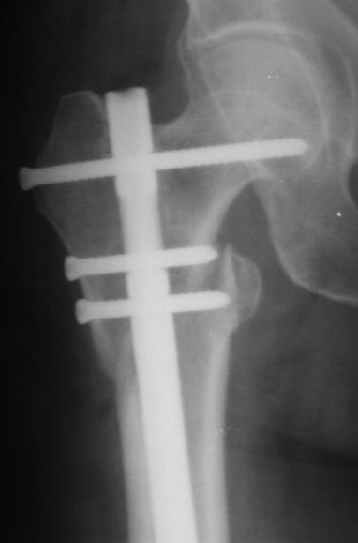

При межвертельных переломах с цефаломедуллярными гвоздями бывает, что проксимальый винт проходит или черед периферический отломок, или прямо над ним. И если остался диастаз, то этот винт при осевой нагрузке не дает сблизиться отломкам. Пример такого остеосинтеза в застарелом случае в приложении.

В качестве предупреждающей меры можно долотом разрушить латеральную стенку дистального отломка под винтом.